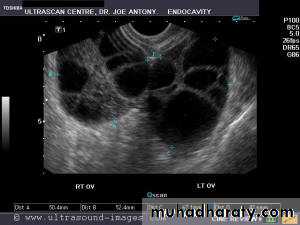

This young adult female patient was examined to evaluate the uterus and ovaries. She was under treatment for infertility and was using gonadotropins. Ultrasound images of the ovaries show grossly enlarged ovaries with large cysts (measuring 2.6 to 3 cms.) in both ovaries. These ultrasound findings are diagnostic of OHSS or ovarian hyperstimulation syndrome.

• Ovarian hyperstimulation syndrome (OHSS):

The ultrasound image again show hyperstimulated ovaries. Both ovaries are grossly enlarged and cystic.